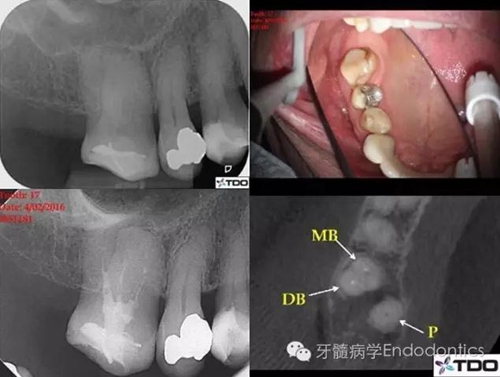

該上頜磨牙盡管位于第一磨牙的位置,但是解剖結(jié)構(gòu)類似第二磨牙。初診時醫(yī)生尋找到3個根管,近中頰根具有粗大、卵圓形的根管口,常見于具有融合根的上頜第二磨牙。醫(yī)生為確定近中頰根僅有一個根管,氫氧化鈣封藥后拍攝CBCT。CBCT上近頰根似乎只有一個居中的根管,醫(yī)生不確定MB根管是否在下段存在二分叉(圖1)。

圖1